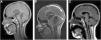

Mujer de 11 años, diagnosticada a raíz de un cuadro de hipertensión intracraneal de tumoración pineal en la RM (fig. 1A) con elevación de αFP y ß-HCG en suero y LCR (tabla 1). Ante la sospecha de tumor de células germinales no germinoma (TCGNG) se inicia tratamiento (protocolo SIOP GCT II) con quimioterapia. Al mes presenta empeoramiento neurológico, objetivándose en la RM crecimiento lesional a expensas del componente quístico junto con normalización de marcadores tumorales. Se realiza resección quirúrgica completa con hallazgo anatomopatológico de teratoma quístico maduro. Con el diagnóstico de síndrome del teratoma en crecimiento se completa el mismo protocolo de tratamiento. A los 4 meses de finalizarlo mantiene remisión completa y negativización de los marcadores.

Controles de RM (cortes sagitales): A) Al diagnóstico: tumoración sólido-quística en región pineal con hidrocefalia secundaria; tamaño 34×22×21mm. B) Al mes de iniciar quimioterapia con empeoramiento clínico, y con aumento del tamaño y del componente quístico de la lesión. C) RM a los 2 meses de finalizar el tratamiento con cambios posquirúrgicos como único hallazgo, sin signos de restos tumorales.